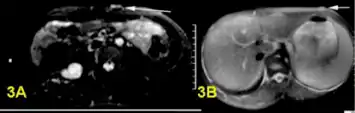

a,b)Bright plexiform neurofibroma